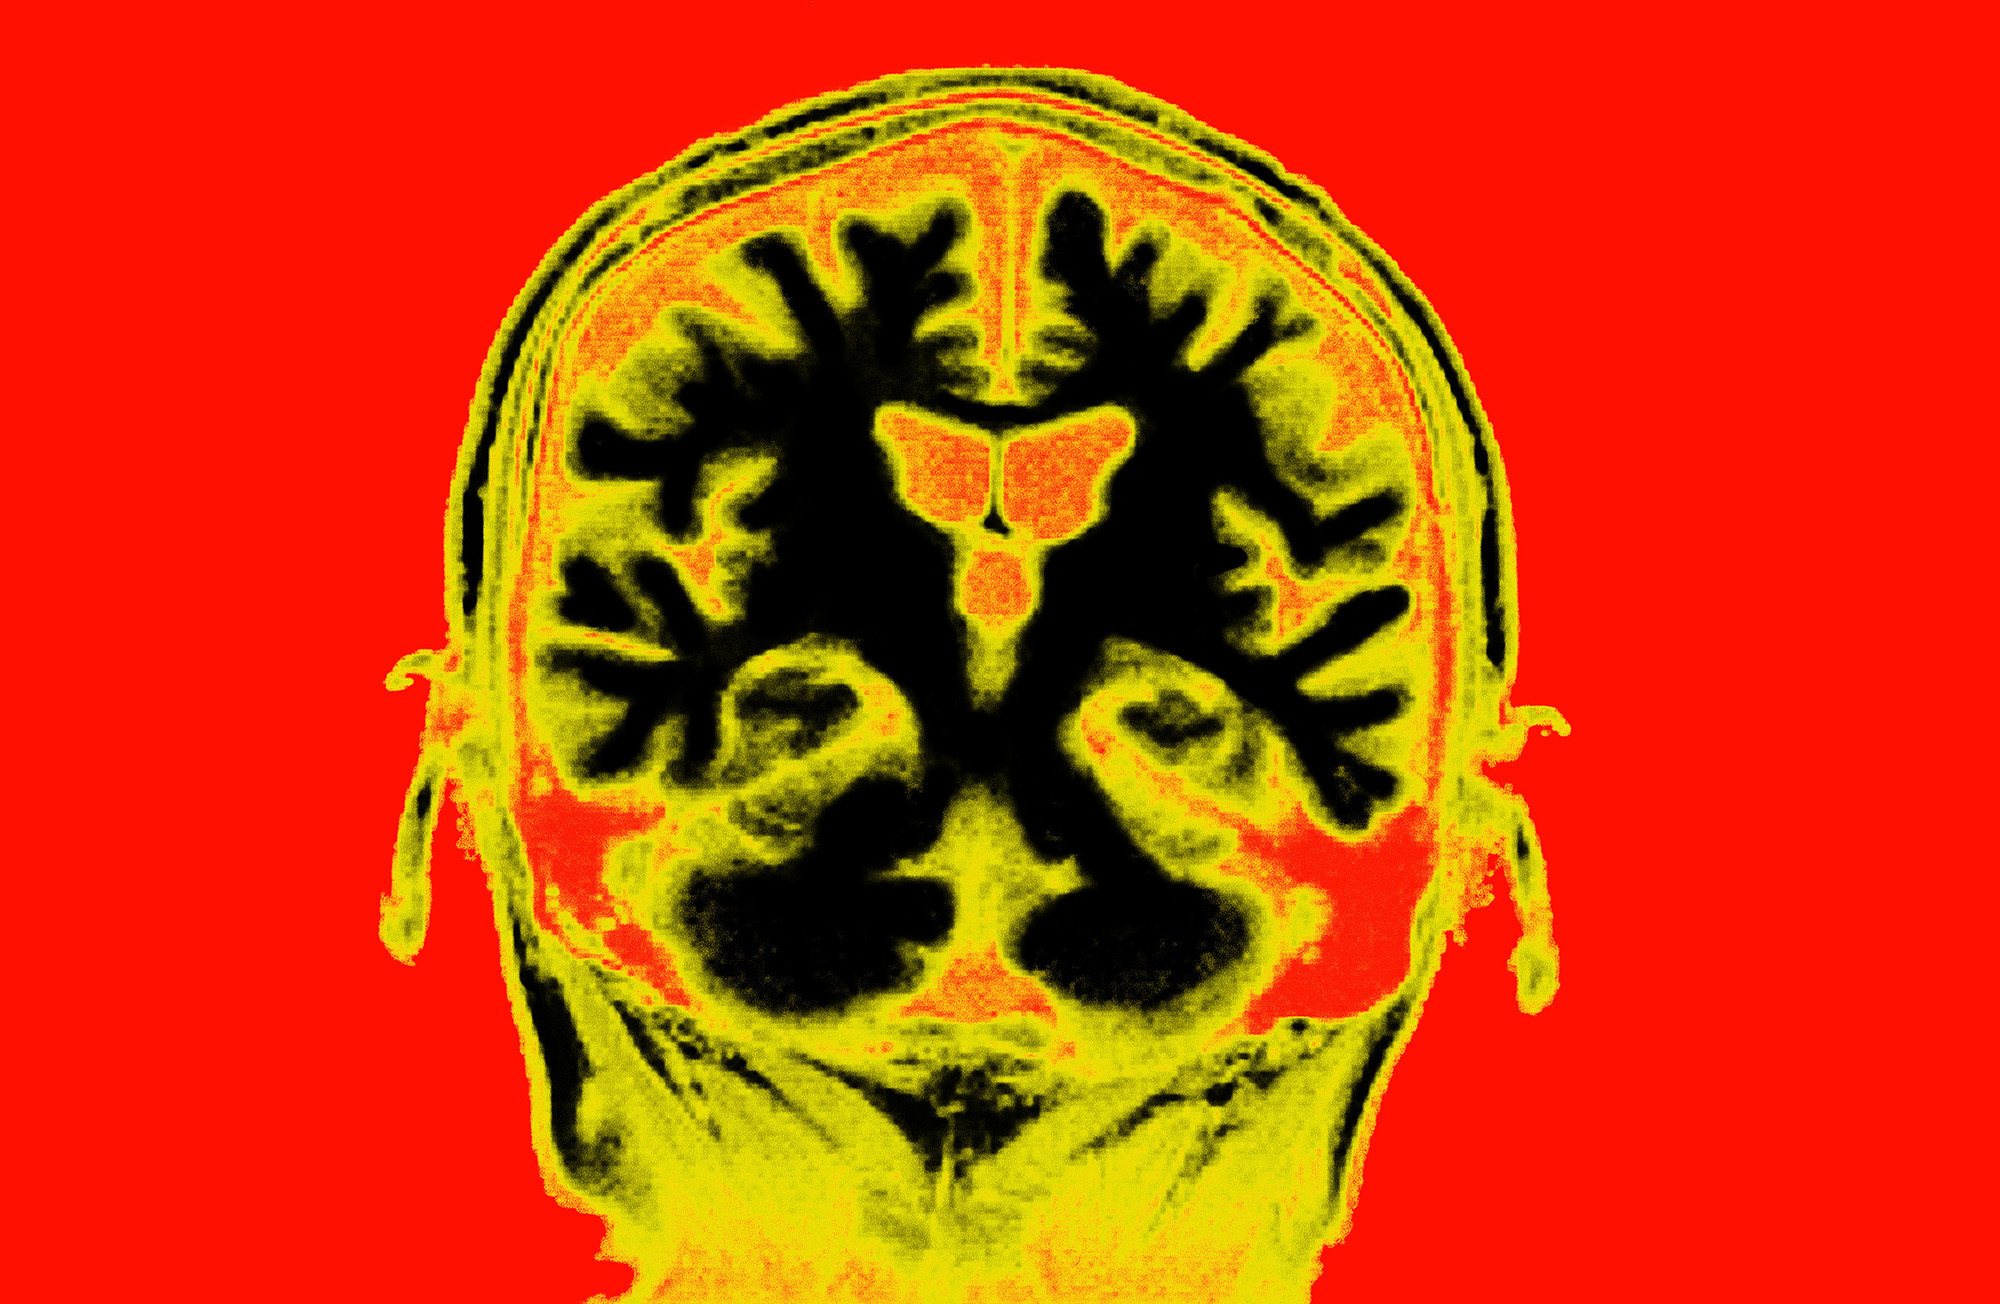

Brain MRI (Collection Mix: Sub/Getty Images)